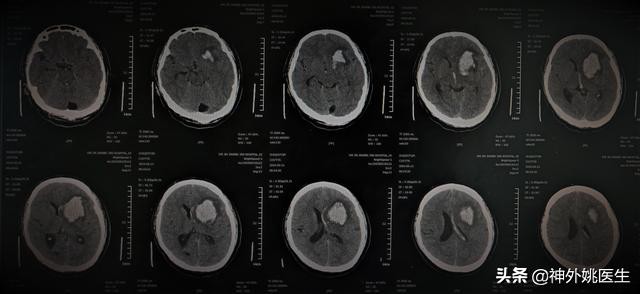

头CT检查:

1、左额叶、基底节区血肿,破入脑室系统。2、大枕大池。(图1)

图1